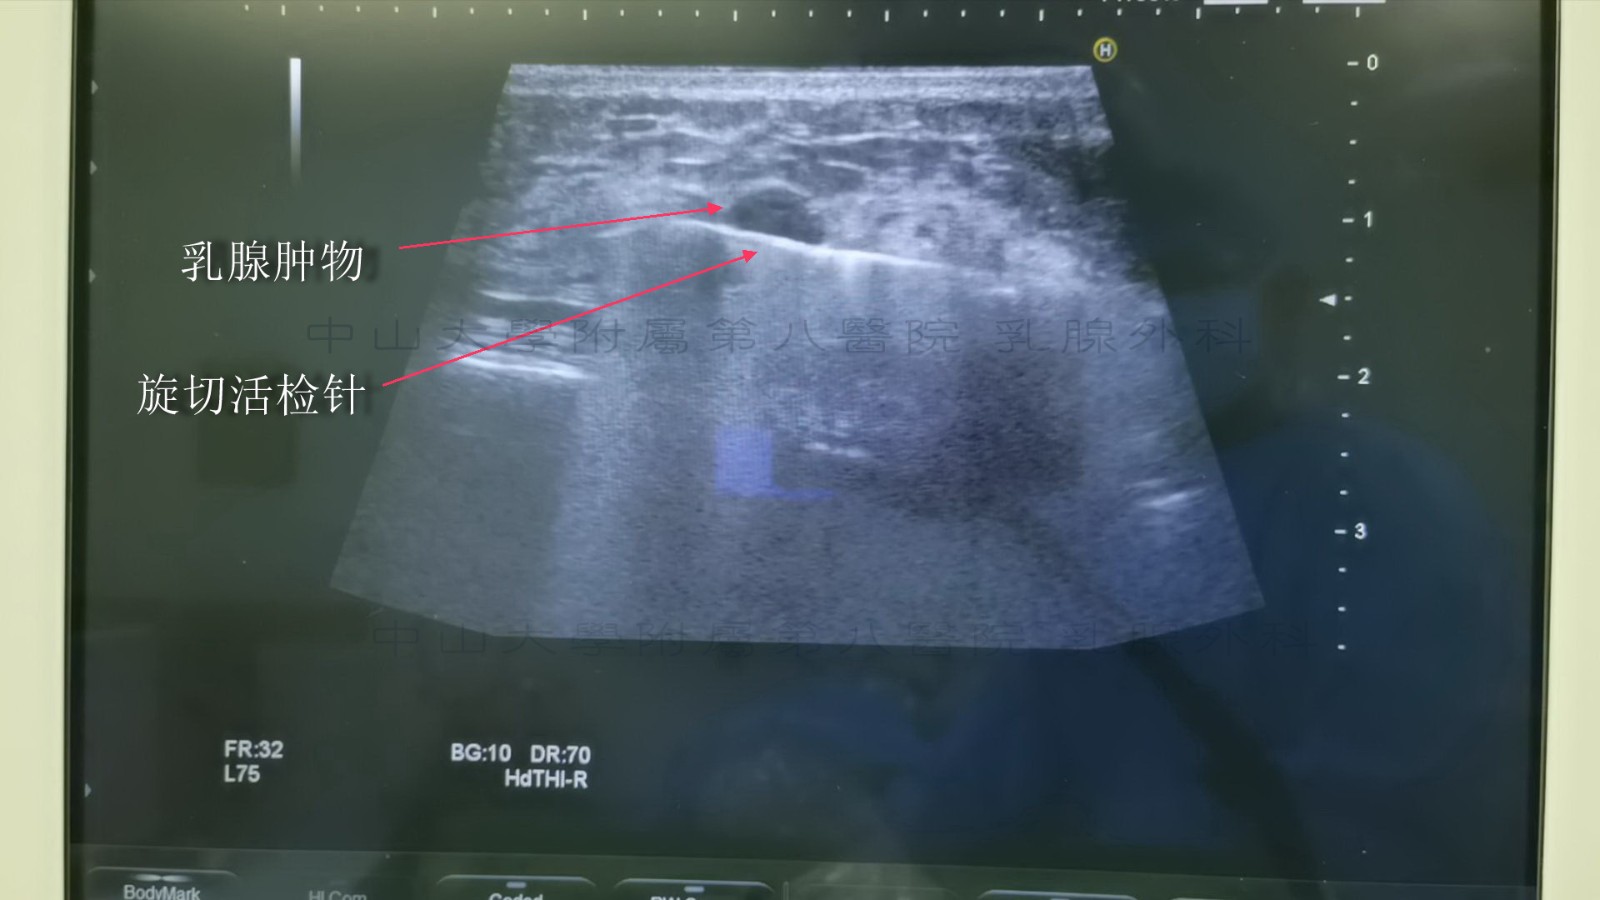

真空辅助乳腺活检(vacuum-assisted breast biopsy,VABB)系统是影像学引导的乳腺活检系统,由真空泵和旋切刀组成。旋切刀通常采用中空管腔设计,所带有的凹槽通过负压吸住待切除部位并完成旋切过程。真空装置由电脑控制保持负压抽吸乳腺病灶,进行旋转切割;通过标本运送系统将切取的标本运出体外。全部操作通过单次穿刺就能准确、简便地收集多个连续样本。超声引导下VABB 是一种多数在局部麻醉下进行的微创手术,皮肤切口仅3~5 mm;在超声定位引导下将活检探针穿过皮肤,到达目标病灶下方;在负压吸引下,将病灶组织吸入旋切刀的收集槽中进行旋切,直到完成拟定的切除操作。整个过程是在高分辨率声像图监控下的可视性操作,其定位准确,操作便利,具有良好的美容效果,可达到临床诊断和治疗的目的,已经成为乳腺外科常用的操作技术。

下图示为超声下定位肿物

下图示为将旋切针负压槽置于肿物下方

下图示为对肿物进行旋切(下图可见肿物吸入负压槽中)